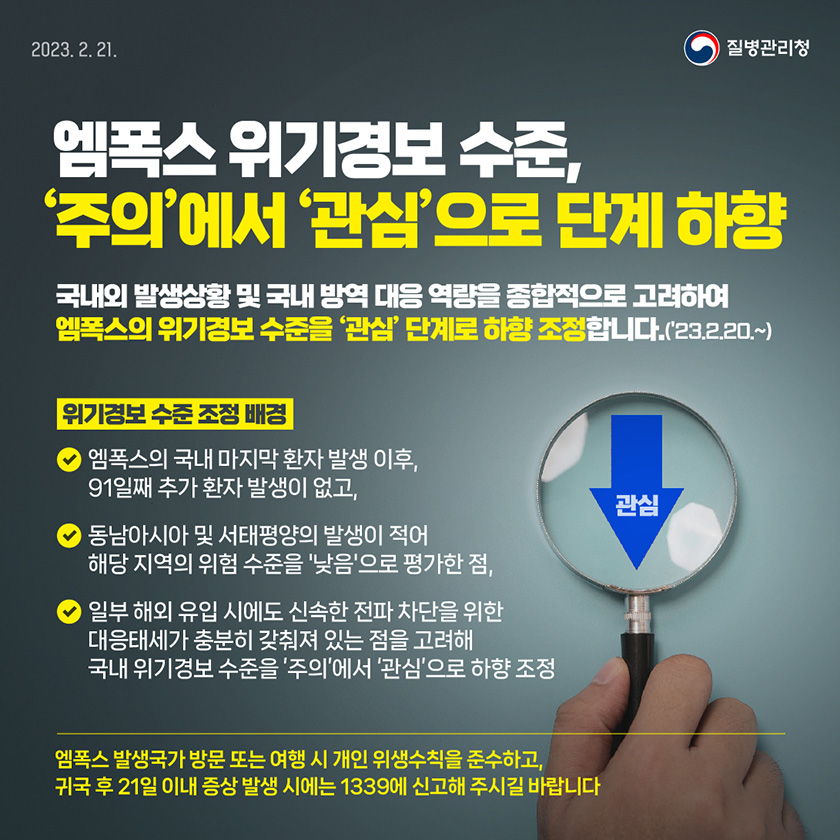

엠폭스 위기경보 수준 주의에서 관심으로 단계 하향 홍보지 홍보자료 알림 자료 질병관리청